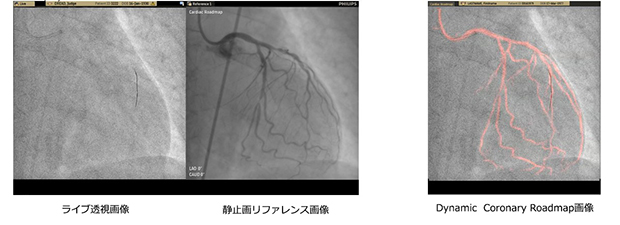

「ダイナミックコロナリーロードマップ(Dynamic Coronary Roadmap)」

フィリップスが新規に開発したダイナミックコロナリーロードマップは,これまでにない新しいPCI治療支援の動画オーバーレイ表示によるロードマップ機能。*1

直前の撮影画像からリファレンス画像となる動画マスク画像集を作成し,カテーテル治療実施時のライブ透視画像に自動で同期オーバーレイ表示し,目的とする治療疾病部位へのアプローチを支援する。また,造影剤が満たされていない状況でも心臓冠動脈の走行が視覚化されたダイナミックコロナリーロードマップ機能により,カテーテルやガイドワイヤーの操作の安全,正確そしてスピーディーな実施を支援する。